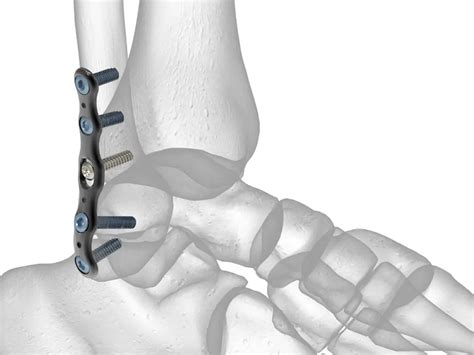

La cirugía se recomienda cuando la fractura está desplazada, el tobillo es inestable o hay fragmentos óseos significativos. Durante el procedimiento, los fragmentos óseos se reposicionan (reducen) a su alineación normal y se fijan con dispositivos como tornillos, placas metálicas o varillas internas.

Tras la cirugía, es necesario un período de descarga para proteger la reparación y evitar que la reconstrucción se desmonte. La recuperación puede variar entre 2 y 5 meses.